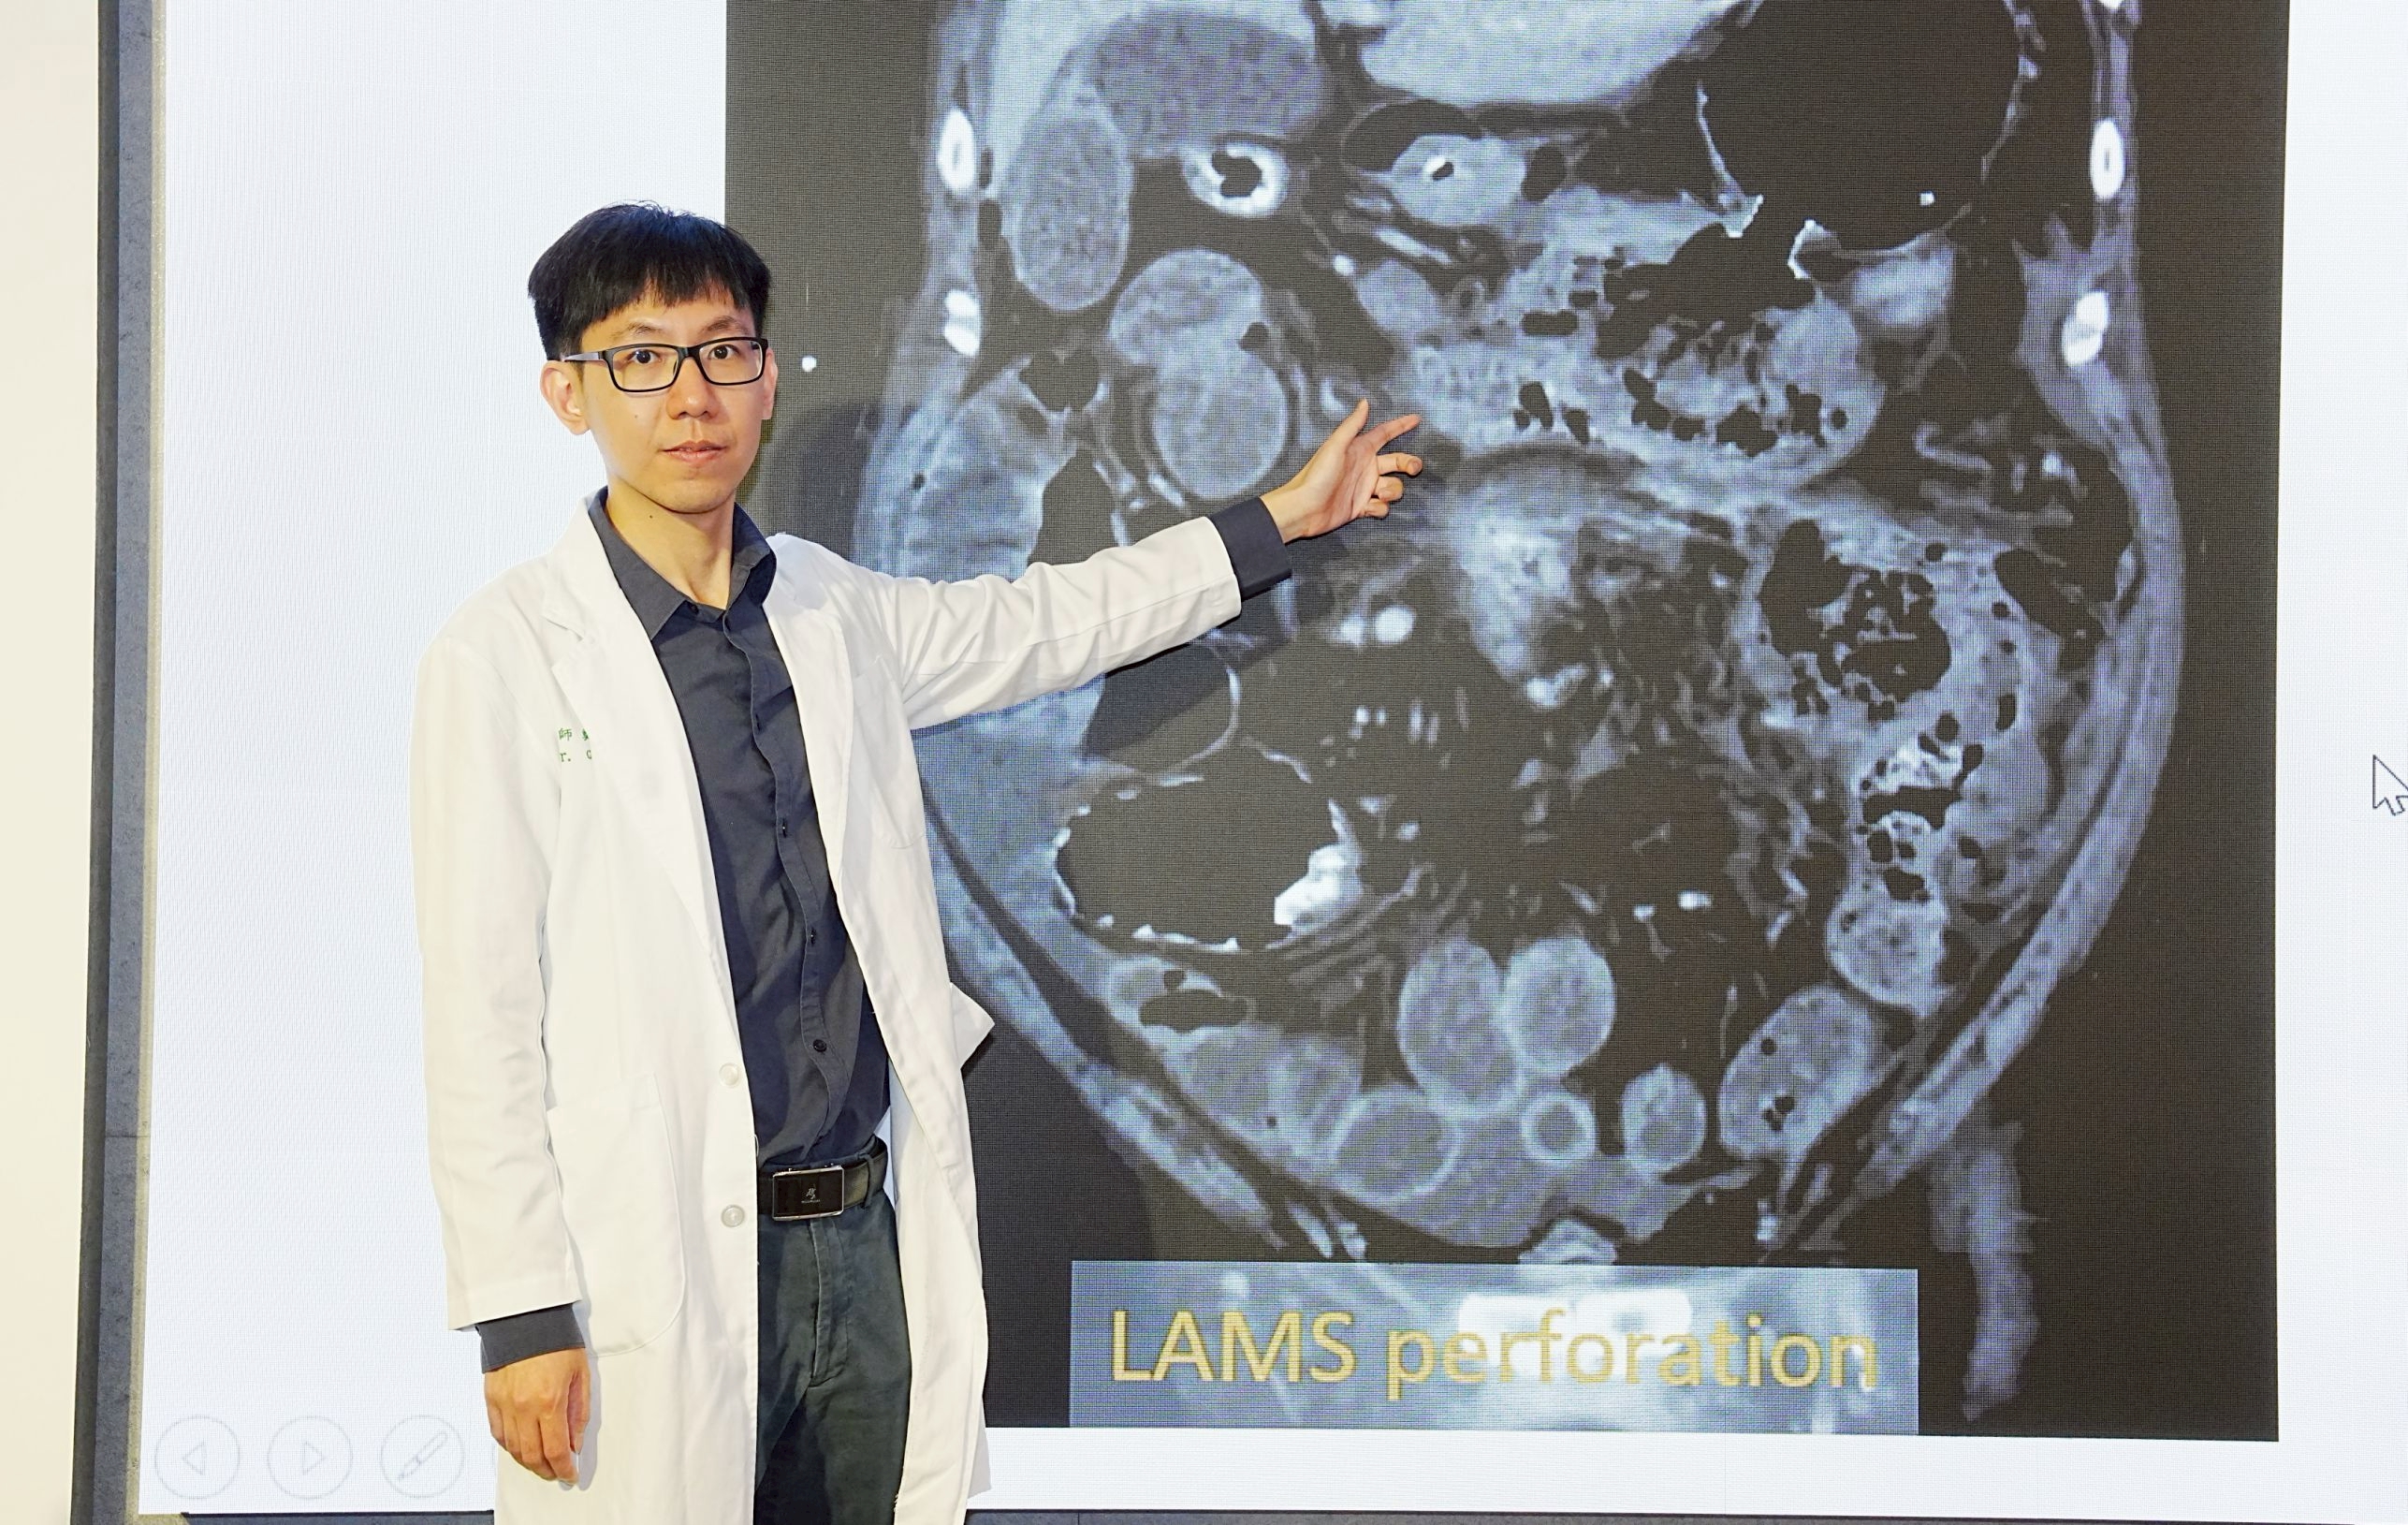

圖:鄭智忠醫師表示針對壞死性胰臟炎治療,過去傳統為開腹清創,傷口大且併發症多,病人身體負擔沉重;近年積極導入國際主流「延遲介入、優先微創」四階段整合治療,先改善胰臟及身體狀況,依病人感染與壞死範圍選擇治療,大幅提升存活率

圖:鄭智忠醫師表示針對壞死性胰臟炎治療,過去傳統為開腹清創,傷口大且併發症多,病人身體負擔沉重;近年積極導入國際主流「延遲介入、優先微創」四階段整合治療,先改善胰臟及身體狀況,依病人感染與壞死範圍選擇治療,大幅提升存活率

圖:鄭智忠醫師表示針對壞死性胰臟炎治療,過去傳統為開腹清創,傷口大且併發症多,病人身體負擔沉重;近年積極導入國際主流「延遲介入、優先微創」四階段整合治療,先改善胰臟及身體狀況,依病人感染與壞死範圍選擇治療,大幅提升存活率

圖:鄭智忠醫師表示針對壞死性胰臟炎治療,過去傳統為開腹清創,傷口大且併發症多,病人身體負擔沉重;近年積極導入國際主流「延遲介入、優先微創」四階段整合治療,先改善胰臟及身體狀況,依病人感染與壞死範圍選擇治療,大幅提升存活率